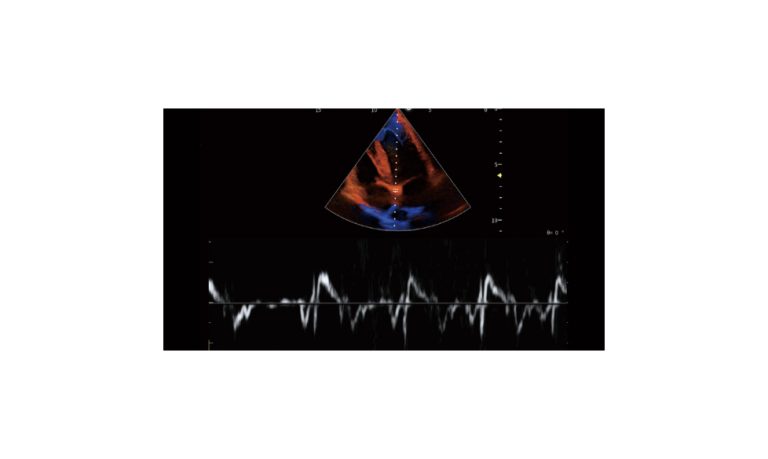

SonoScape Pro Pet E11

Smart Imaging

Introducing the first portable ultrasound with the C-Field+TM platform, redefining diagnostic imaging. Designed for veterinarians, it delivers unmatched clarity, ultra-fast processing, and seamless adaptability for all species. Experience Smart Imaging, Heartfelt Care—anywhere.

Equipped with cutting-edge veterinary software and optimized workflows, it embodies our commitment to Smart Imaging, Heartfelt Care – Wherever Their Journey Leads, with unparalleled performance and adaptability, this innovative system empowers veterinarians to provide exceptional care across all diagnostic applications,